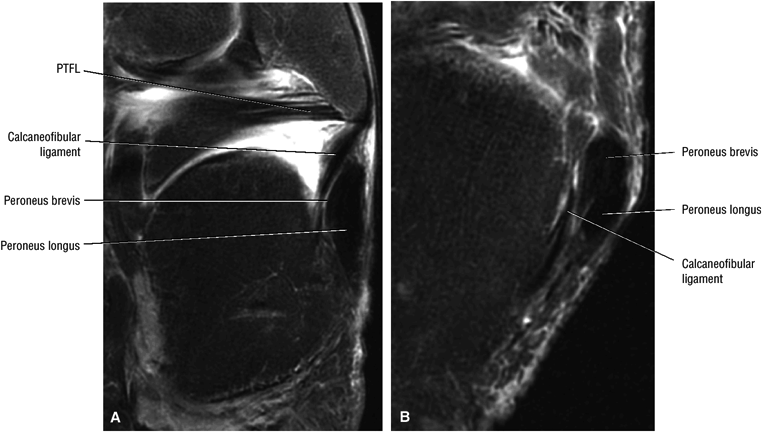

|

![]() |